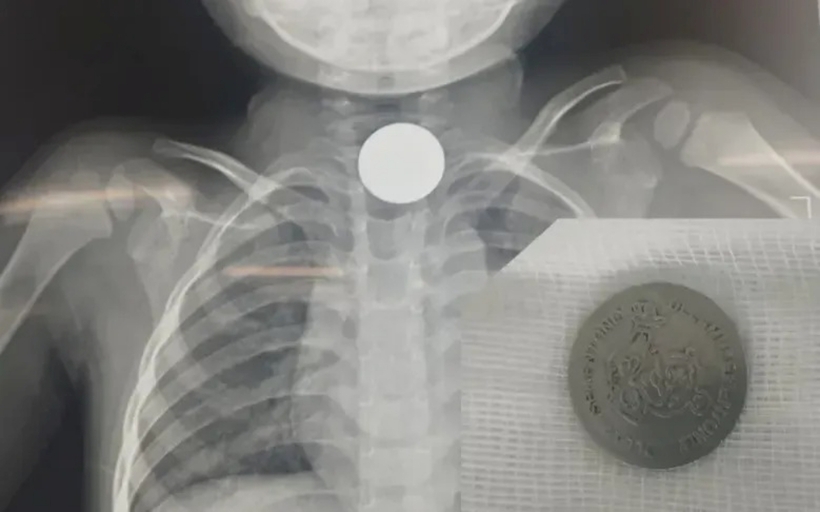

Theo VTV Times, Bệnh viện Nhi đồng Đồng Nai vừa thực hiện thành công ca nội soi gắp đồng xu kim loại có kích thước 20mm ra khỏi thực quản bệnh nhi 3 tuổi.

Sau khi thăm khám và chụp X-quang, các bác sĩ xác định có dị vật kim loại nằm trong thực quản của bệnh nhi và nhanh chóng tiến hành nội soi lấy dị vật.

Phim chụp X-quang và dị vật là đồng xu kim loại có kích thước 20mm được gắp ra ngoài. Ảnh: VTV Times